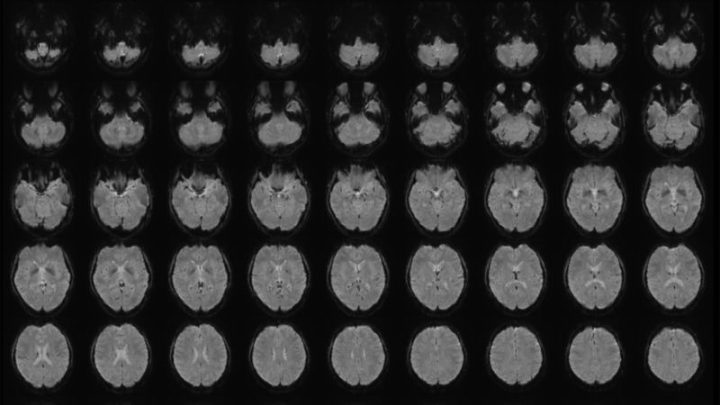

Scientist turns people’s mental images into text using ‘mind-captioning’ technology November 14, 2025 By admin A scientist in Japan has developed a technique that uses brain scans and artificial intelligence to turn a person’s mental images into descriptive sentences.